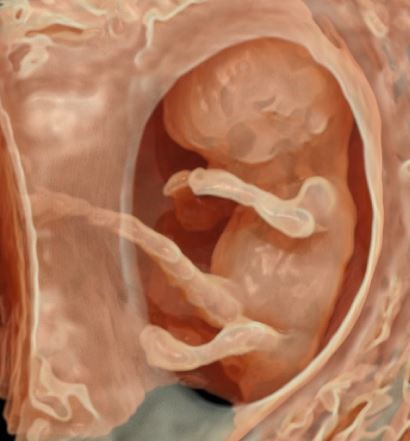

Ultrasound is a type of imaging technology which uses sound waves to create images. During pregnancy, a transducer is placed on the belly or in the vagina. The transducer emits sound waves that travel through the baby and emit echoes. The transducer picks up these echoes and forms the image of your baby on the screen.

The scan is performed by the doctor in a dimly lit room to get good images of the baby. You will be asked to lie down on the couch, expose your tummy and tissue paper is tucked around your clothing to protect it from soiling due to the gel used. Ultrasound gel is put on your tummy and the doctor moves a probe over the skin. You could watch the scan on the screen in front of you. The scan does not hurt you but slight pressure needs to be applied occasionally to get a better view of the baby. You will be asked to inform the doctor if it hurts you during the scan. In advanced centers like ours, a 3D/4D probe is used to see the parts of your baby and for detailed examination.